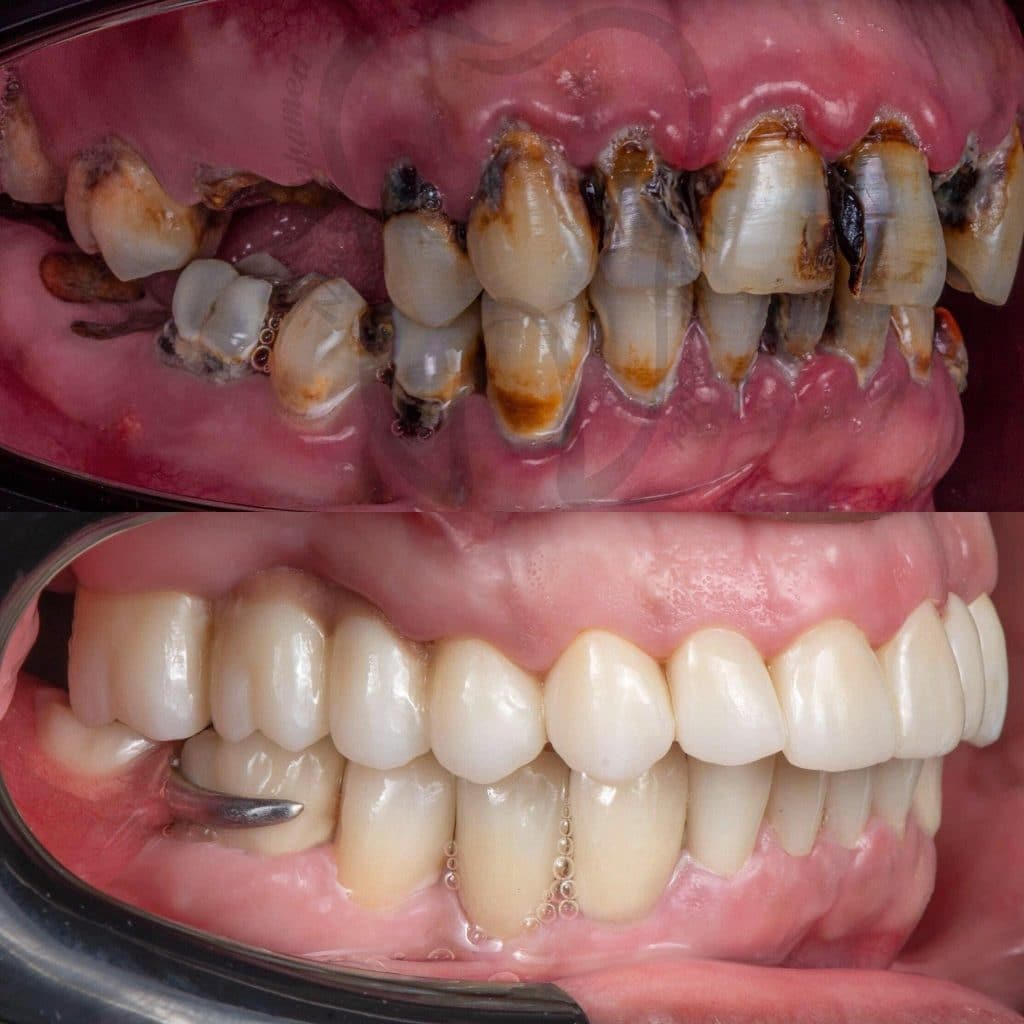

Our treatment plan included:

📌 10 Extractions

📌Full Mouth scaling and Root planing

📌 12 Endodontic treatment

📌 6 Post and Core

📌 Full Mouth Composite Restoration

📌 20 Unit Zirconium

📌 5 Unit PFM

📌 Lower Arch Class I Metallic RPD